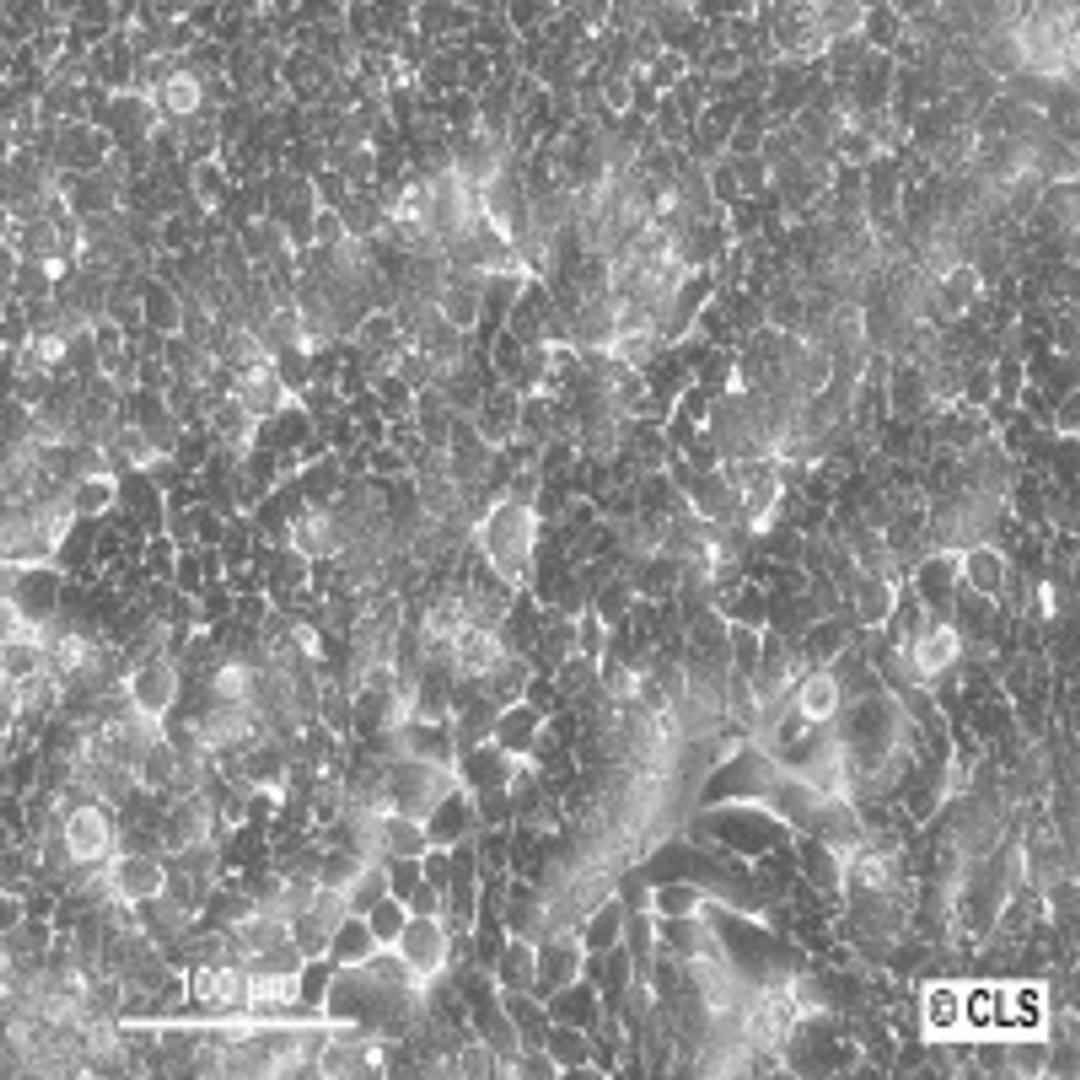

HT-29

Human Colon Adenocarcinoma, G II cell line. Frozen cryovial. 4.5 Mio. cells/ml.

Human Colon Adenocarcinoma, GII, cell line HT-29

Morphology: epithelial

Growth Properties: adherent